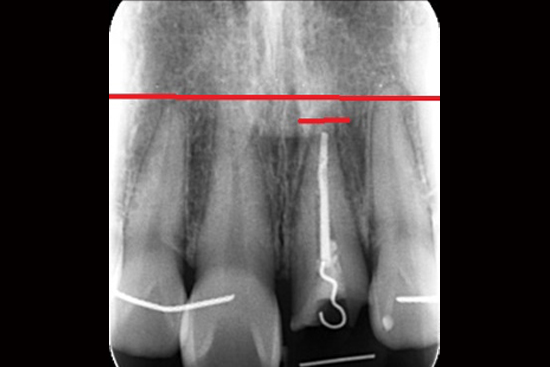

case 3.

治療前

治療中

治療後

| 主訴 | かぶせ物の中で深くなってしまった虫歯を治したい |

|---|---|

| 治療期間 | 約3ヶ月 |

| 治療費 | 5万(税抜) |

| 治療内容 | エクストリュージョン 深くなってしまった虫歯や割れてしまった歯など、本来抜かなければいけない歯を部分矯正によって、残すことができる。 |

| 治療の リスク |

歯が揺れてしまう可能性 |